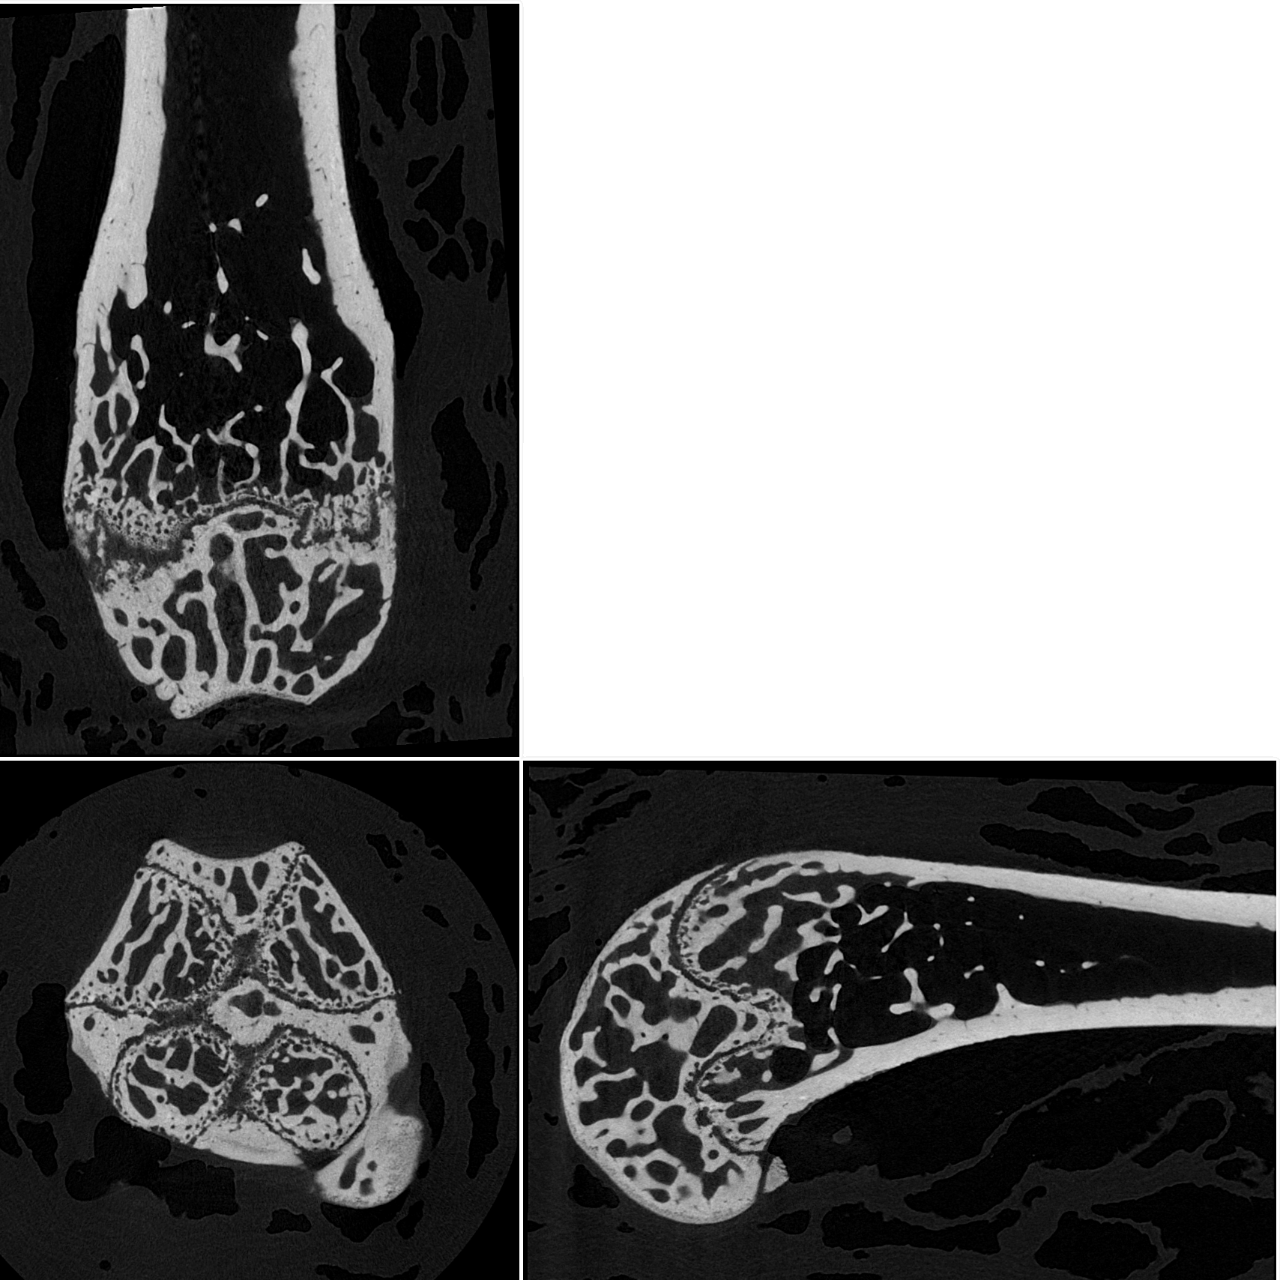

Orthogonal slices through a mouse femur, scanned at 2.8 µm voxel size.